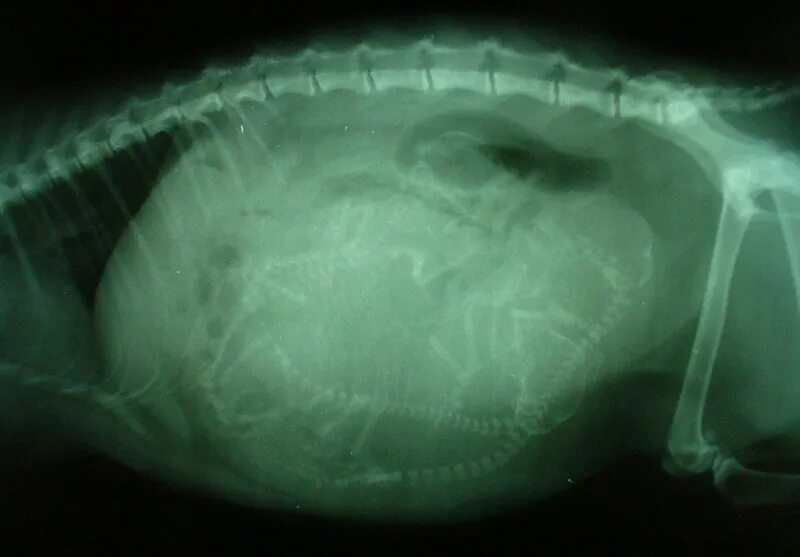

Какой срок беременности у кошек